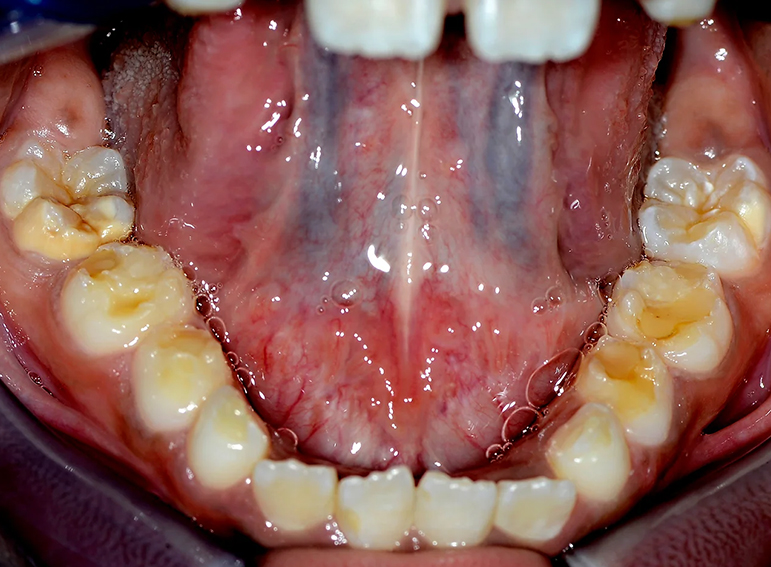

Hypoplastic primary molars: Placement of hall crowns, extraction of URD and ULD, composite restorations of LRD, LLD and C’s and fissure sealants of adult molars.